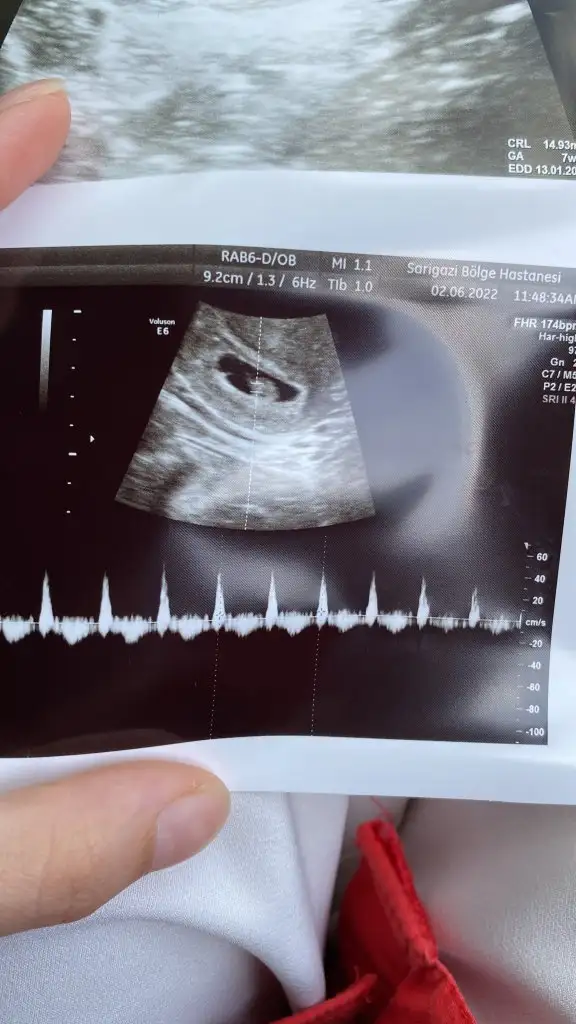

Merhabalar 7+6 karından 🤩

Buda bizim 7+2 görüntümüz 😊